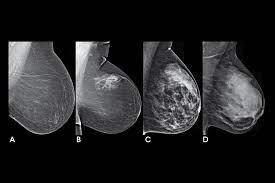

A mammogram uses X-rays (ionizing radiation) to create images of the inside of the breast to check for cancer and other conditions. It can be used for screening to detect cancer, for instance, before there’s a lump in the breast, or to assist in the diagnosis of cancer. Radiologists use mammograms to interpret, and classify breast density into four categories.

A, B, C, D’s of Breast Density and Mammograms

Dense breasts are common findings after a mammogram, and are not considered a disease, or an abnormal condition. However, they are a risk factor for a woman to develop breast cancer. According to doctors at Memorial Sloan Kettering, women with extremely dense breast tissue “are four to six times more likely to get breast cancer than people with the least dense breasts.”